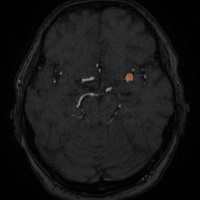

Das Modul Aneurysmadetektion ermöglicht die zuverlässige Detektion von intrakraniellen Aneurysmen. Durch die Auswertung von TOF-Sequenzen werden Anzahl, Volumen und Dynamiken im Zeitverlauf schnell erkannt.